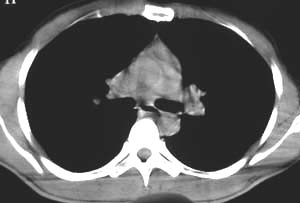

标题: CT5150:左上肺空洞病变,肺撕裂伤?

左侧锁骨骨折,患者主诉未伤及胸部,无其他病史。

该病灶在纵隔窗没有显示,说明是渗出性病变,而且肺窗看起来也显得它非常淡薄。能造成锁骨骨折,说明受伤时所受冲击力不小。在大冲击力的情况下,胸部发生碰撞的机会非常大,很多患者在受伤后都说不清自己究竟是怎么着地以及究竟是何种姿势受伤。

所以我认为应该首先考虑创伤性湿肺,只是需要楼主详细询问病史,排除炎性感染的可能。

没有详细的病史,影象上是渗出性改变,中心病灶有空洞存在结核  湿肺 都有可能,那肺泡癌可以除外吗?

从病灶特点分析应该是渗出性病灶,但有一点不好解释.病灶中心有空洞,而且不规则,空洞边缘似见硬化或钙化.因此考虑:肺挫伤同时不除外特殊感染性病灶.

有明确的外伤史,病灶呈渗出性改变,密度较低,边缘呈晕圈状改变,周围未见明显的异常血管影及纤维索条影和卫星灶。所以考虑是创伤性湿胸。

左肺上叶前段磨玻璃样结节,中心可见小结节样高密度影及空泡影,我个人觉得首先考虑恶性结节,结合病史,不能完全排除肺挫伤!建议薄层扫描后多方位重建,观察与支气管关系;定期复查,追踪观察(此类病变可能很长时间内不会发生改变),如果结节样高密度成分增多,建议手术切除.